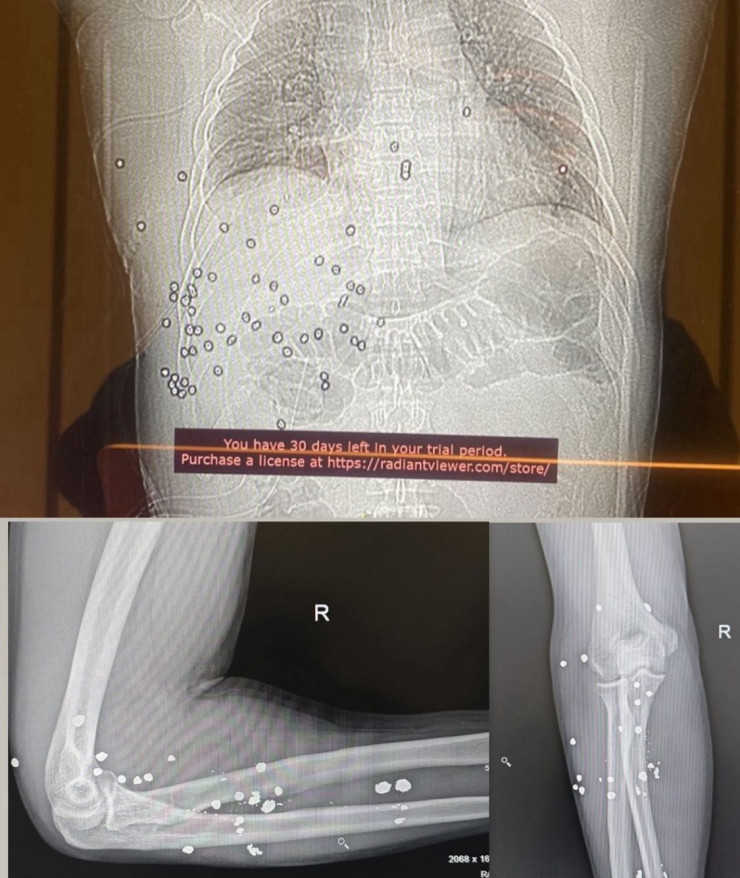

Сот басталған күні Руслан Берденов әлеуметтік желідегі парақшасында өзінің денесінде әлі де 60-тан астам аңшылық қарудан шыққан оқ қалдығы бар екенін жариялап, осы себептен сотқа қатыса алмағанын түсіндірді.

"Қандай да бір спекуляциялар, манипуляциялар немесе жалған айыптаулар мені өз жолымнан тайдырмайды. Мен әлі де адал, ашық әрі әділ сотқа сенемін. Денемде әлі де 60-тан астам аңшылық қарудан шыққан оқ қалдығы бар. Бұл – құжатталған факт", – деп жазды Руслан Берденов және рентген суретін жариялады.